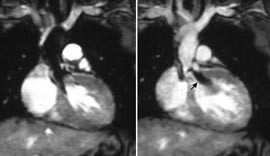

Cine-MR med gradientekkoteknikk gir relativt dårlig kontrast mellom de ulike bløtdelene, men god kontrast mellom sirkulerende blod og omgivende stasjonært vev. Normalt sirkulerende blod blir lysegrått eller hvitt, mens de fleste stasjonære vev har ulike mellomgråtoner (fig 2). I områder med turbulent blodstrøm forsvinner imidlertid signalstyrken i blodet. En jet av blodstrøm gjennom en stenotisk klaff eller en septumdefekt, eller en regurgitasjon gjennom en insuffisient hjerteklaff, vil derfor sees som en svart dusj i det ellers hvite blodet (fig 3). Basert på cineopptakene kan man beregne parametere som endediastolisk og endesystolisk ventrikkelvolum, ejeksjonsfraksjon og muskelmasse. Selve cinefremvisningen gir også detaljert informasjon om regional myokardkontraksjon, så som hypokinesi, akinesi og paradoks (invers) bevegelighet.